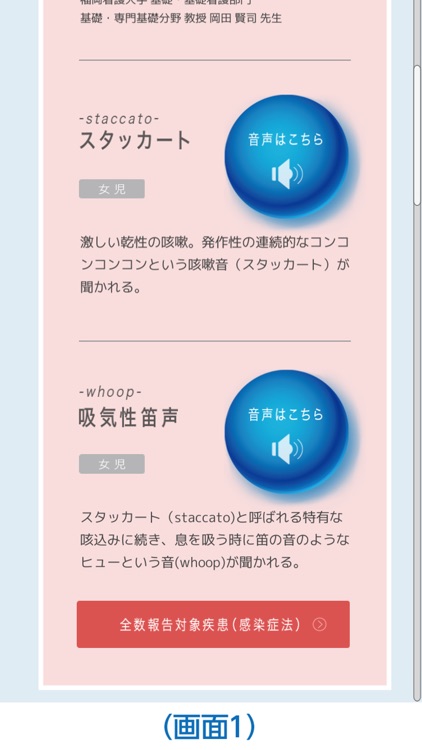

①ネット環境の有無によらず、咳の音※をすぐに再生できます。

問診の際の参考としてお役立てください。(画面1)

※百日咳、マイコプラズマ感染症、肺非結核性抗酸菌症、後鼻漏症候群(副鼻腔炎による咳)